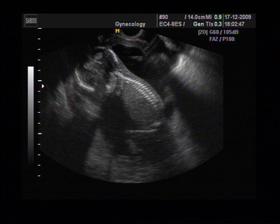

8/10 jsme se byli podívat u paní doktorky, zda testy nelhaly - a ono n e. Puclík měřil 0,37cm a co je důležité - srdíčko už funguje. Táta s Pepínem byli v ordinaci s námi, a když se na monitoru objevilo mimi, tak ho Pepíno pozdravil - udělal mu "ahoj" 🙂 oba nás to s Honzou dojalo. Další kontrola 22/10.